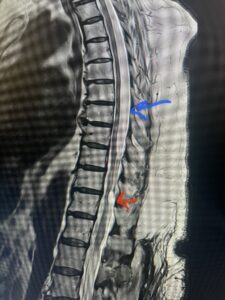

This 67-year-old female presents with progressive heaviness and numbness of the legs and difficulty ambulating. Her right leg was worse than her left. She had right greater than left hip flexor weakness. She was hyperreflexia in her lower extremities. An MRI (Fig. 1) demonstrated an intradural arachnoid cyst at T10-11 with severe spinal cord compression. She also appeared to have an arachnoid cyst above from T4-T8 with anterior displacement and compression of the spinal cord. Because of her severe myelopathy and the findings on MRI the patient underwent laminectomy for surgical decompression of cyst. Intraoperatively the focal arachnoid cyst at T10-11 appeared as a small bubble crushing the spinal cord anteriorly with scarring of the arachnoid with no CSF flow above or below.

Fig. 1 Sagittal T2-weighted thoracic MRI demonstrating both T10-11 focal intradural arachnoid cyst (red arrow) and larger upper thoracic cyst that appears to extend from T4-T8 (blue arrow).